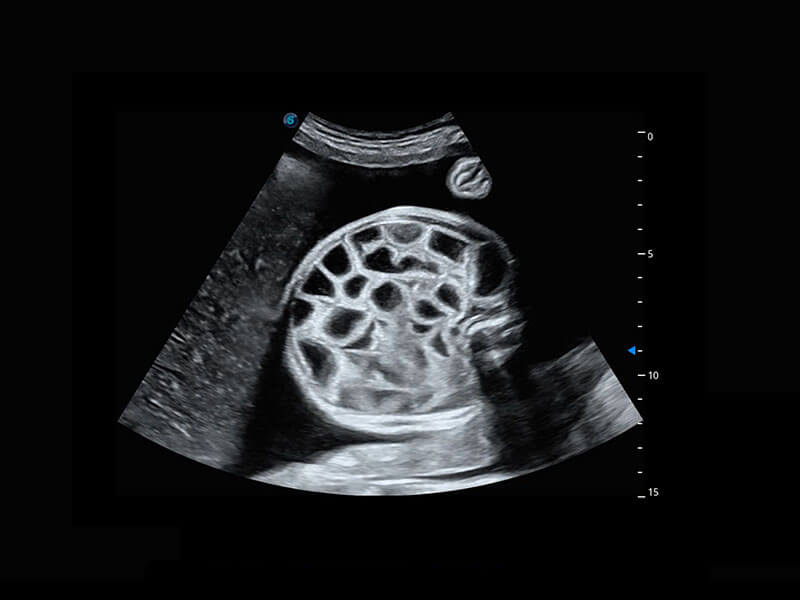

P60搭载一系列胎儿心脏成像技术,实现精细的胎儿心脏评估。

四腔切面

四腔心血流

右室双出口

胎心容积成像